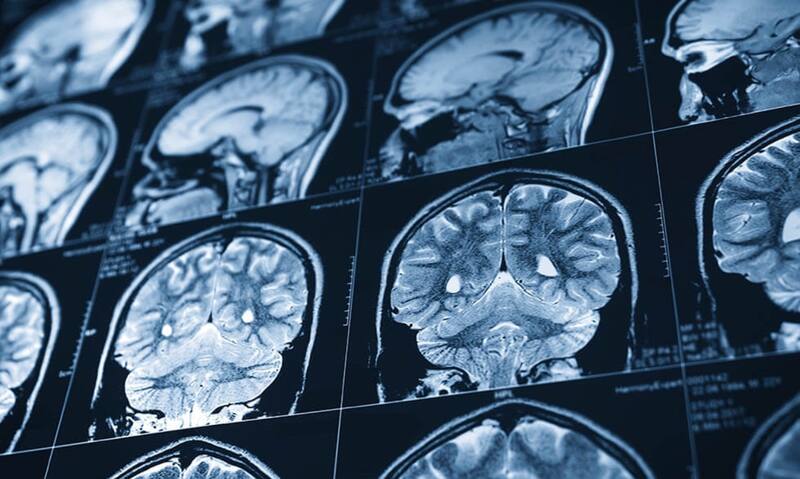

Cuando se habla de un accidente cerebrovascular (ACV), se alude a una emergencia médica que se desencadena cuando hay una interrupción del suministro de sangre hacia el cerebro.

O también, cuando existe un sangrado dentro de este órgano, según detallan desde el Ministerio de Salud de Chile en un artículo publicado a finales del año pasado.